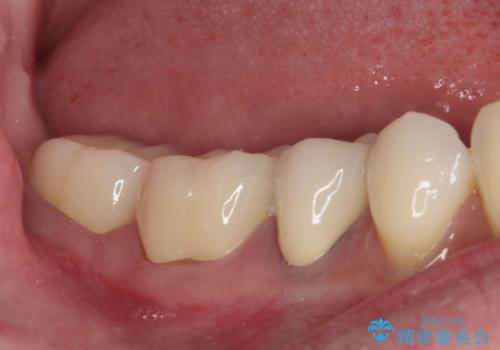

歯とクラウンの適合が良くなることで、食事の度にしみるという症状はなくなり、歯間部にものが挟まって不快な思いをすることもなくなりました。